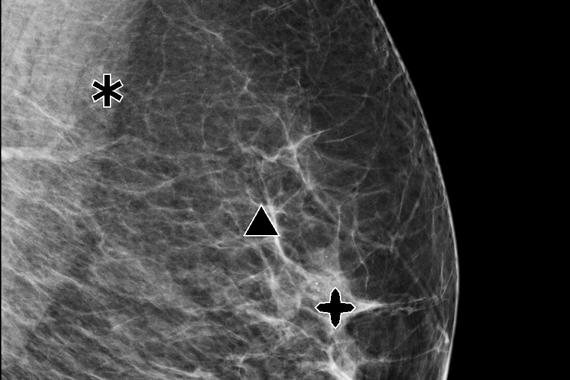

Hologic Selenia® Dimensions, FDA onaylı Genius™ 3D tomosentez teknolojisi ile meme dokusunu yüksek çözünürlükte katman katman tarar. Bu ileri teknoloji, geleneksel 2D mamografiye kıyasla meme kanserini %20 ile %65 arasında daha yüksek oranda tespit ederek erken teşhiste önemli bir avantaj sunar. Klinik çalışmalar, bu sistemin yalancı pozitif çağrı oranlarını %40’a kadar azaltarak gereksiz biyopsi sayısının düşürülmesini sağladığını ortaya koymaktadır. Özellikle yoğun ve karmaşık meme yapısına sahip hastalarda, lezyonların daha net görünmesini mümkün kılarak radyologların tanı güvenilirliğini artırır.

Hologic Selenia® Dimensions, yoğun meme dokusuna sahip kadınlarda bile yüksek çözünürlükte ve detaylı görüntüler sunar. Bu teknoloji, meme dokusunun yoğunluğundan kaynaklanan tanı zorluklarını aşarak, gizli kalabilecek küçük lezyonların tespit edilmesini mümkün kılar. Klinik çalışmalar, bu sistemin yoğun meme dokusunda meme kanseri tespit oranını anlamlı ölçüde artırdığını ve erken teşhiste önemli rol oynadığını göstermektedir. Böylece risk altındaki hastalar için güvenilir ve etkili bir tarama çözümü sağlar.

Hologic’in gelişmiş CAD teknolojisi, mamografi taramalarında potansiyel anomalileri otomatik olarak belirleyerek radyologların tanı doğruluğunu artırır. Görüntüler üzerinde dikkat çekici bölgeleri vurgulayan CAD, erken evre meme kanseri belirtilerinin atlanma riskini azaltır. Bu sayede radyologlar için ikinci bir okuyucu işlevi görerek hem tarama süresini kısaltır hem de tanısal kesinliği destekler. Özellikle yoğun meme dokusuna sahip hastalarda, CAD sistemi lezyon tespiti için ek bir güvenlik katmanı sunar.

Özellikle yoğun meme dokusuna sahip hastalarda, Clarity HD, dokuların üst üste binmesini önleyerek küçük kitleler, gizli kalsifikasyonlar ve diğer anormalliklerin (örneğin spiküler lezyonlar veya distorsiyonlar) daha görünür hale gelmesini sağlar. Bu da erken evre meme kanserinin tespiti açısından kritik öneme sahiptir. Geleneksel 2D sistemlerle karşılaştırıldığında, Clarity HD ile elde edilen görüntü netliği %50’ye kadar artarken, belirsiz tanılar nedeniyle istenen ileri görüntüleme oranları %40’a kadar azalmaktadır.